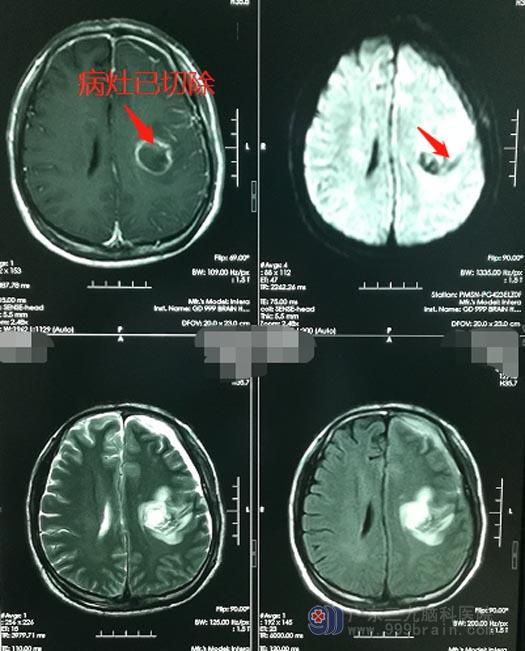

准备完善后,鲁明带领团队在机器人辅助唤醒麻醉下为李大哥施行“左顶叶海绵状血管瘤切除术”。手术很成功,术中出血不多,对功能区的保护十分到位,肿瘤被全部切除。手术后,李大哥生命体征正常,没有出现言语、肢体偏瘫等后遗症,不久就康复出院了。